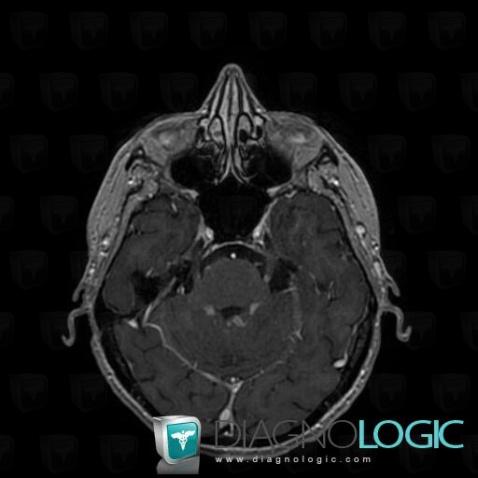

Les images ci-dessous illustrent ce dossier pour les diagnostics Carcinose méningée, Méningite carcinomateuse, pour les modalités (IRM)

Voici les informations spécifiques à l'image clé ci dessus:

- Diagnostic Méningite carcinomateuse, Localisation(s) Espaces peri cérébraux infratentoriels, comportant les gammes Anomalie des citernes de la base

Voici les informations spécifiques à l'image clé ci dessus:

- Diagnostic Carcinose méningée, Localisation(s) Nerfs VII VIII, comportant les gammes Lésion des nerfs VII / VIII

Voici les informations spécifiques à l'image clé ci dessus:

- Diagnostic Carcinose méningée, Localisation(s) Autres nerfs craniens, comportant les gammes Lésion des nerfs craniens